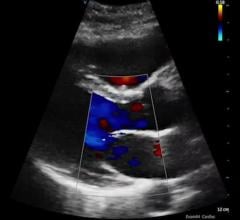

Here are two quick clinical examples of point-of-care ultrasound (POCUS) lung imaging and cardiac imaging using a GE ...

This channel includes news and new technology innovations about cardiovascular ultrasounds. Cardiovascular ultrasounds, or echocardiograms, use ultrasound imaging to provide a picture of the heart.